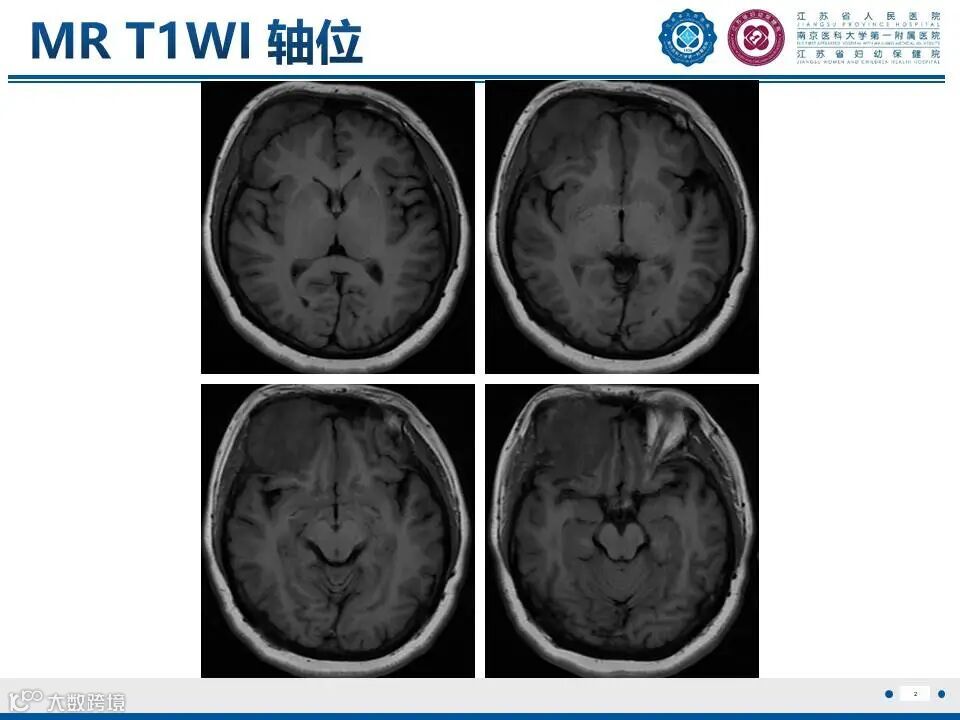

来源:江苏省人民医院放射科